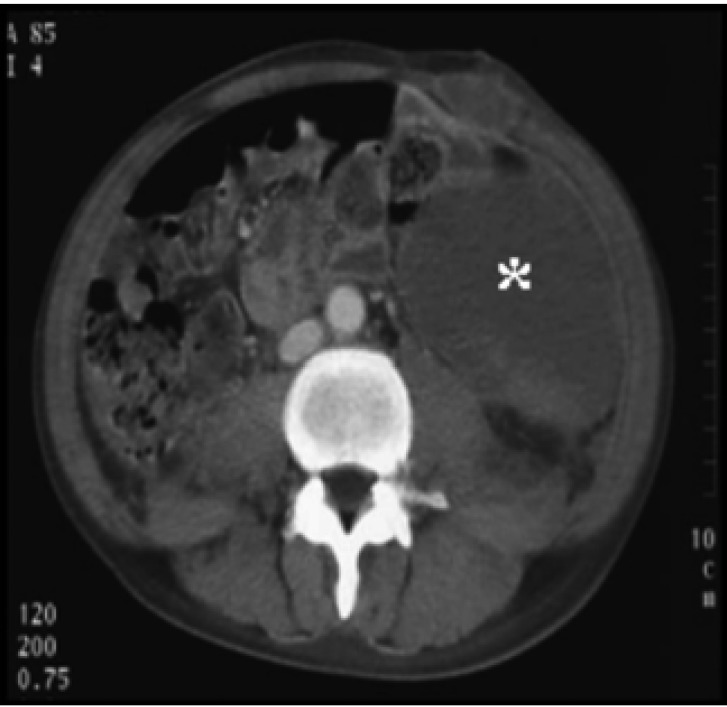

The patient's initial graft function was good. Intraabdominal bleeding had developed just after transplantation, but bleeding was not observed thereafter (Figure 1). His platelet count gradually increased on the tenth post-transplant day and the patient was discharged on the 37th post-transplant day with a normal serum creatinine level (114 µmol/L) and a platelet count of 124,000/µL (Figure 2). The native kidney biopsy findings were consistent with IgA nephropathy (Figure 3).

Figure 1

Abdominal computed tomography image. Note the huge hematoma (asterisk) in the abdominal cavity.